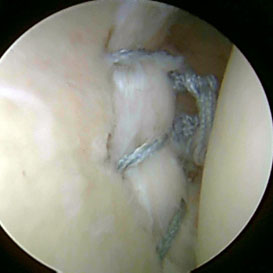

Αρθροσκοπική εικόνα συρραφής μιας ρήξης επιχείλιου χόνδρου (βλάβη Bankart)

(προσωπικό αρχείο κου Τριανταφυλλόπουλου)